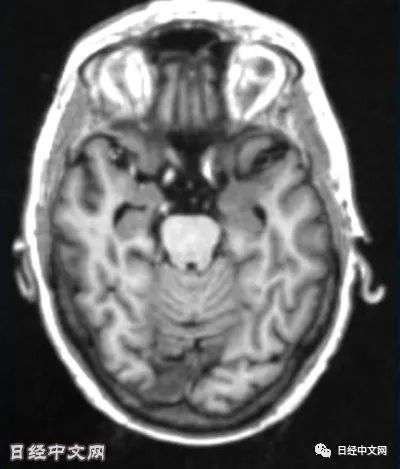

运用AI分析三维脑部核磁共振图像

富士胶片利用与阿尔茨海默症相关的共同研究数据库开发出了AI。2020年夏季,通过AI分析了239名拥有轻度认知障碍症状的患者的数据。据悉,由AI预测这些患者会在2年后发展为阿尔茨海默症,还是保持轻度认知障碍状态。与实际病情进行对照后,准确率达到了85%。